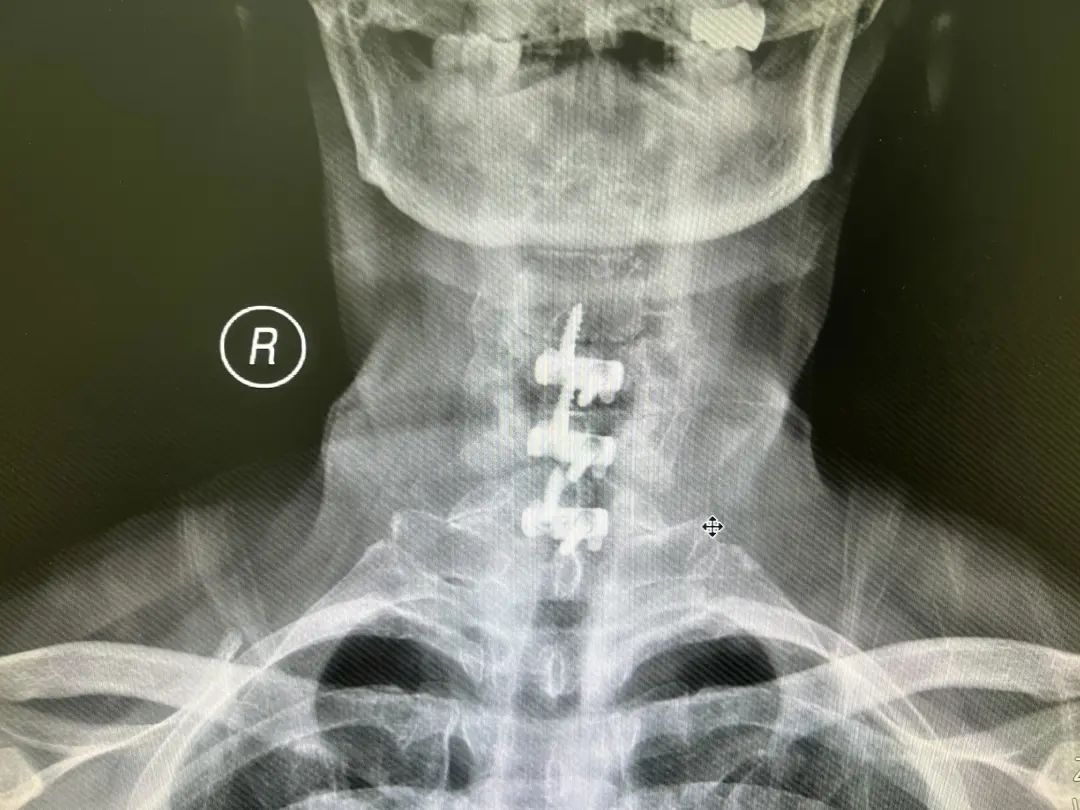

2022年3月9日,在麻醉科及骨伤科四病区的配合下,李智奎副主任医师团队为隆奶奶实施了颈椎间盘切除椎间植骨融合术。在科室医护人员的精心治疗与护理下,术后隆奶奶一切恢复良好,于2022年3月16日出院,出院时隆奶奶告诉医护人员上肢麻木情况已有很大改善。